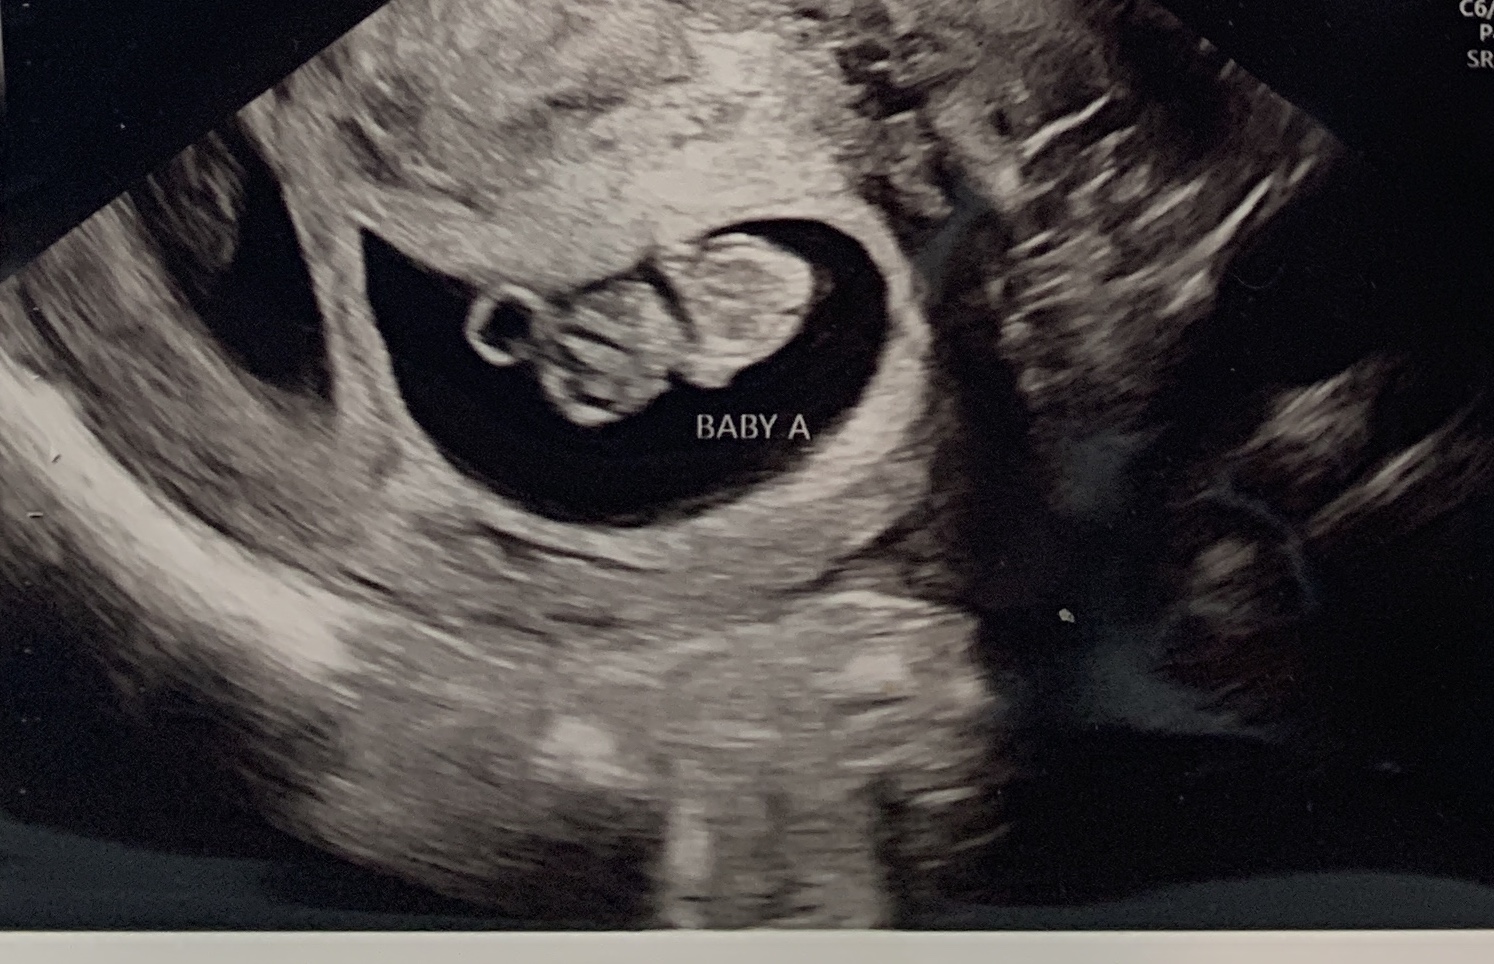

Back with some new ultrasound pics! 12w3d here :)

Attachment 42687

Attachment 42688

While earlier than I like to guess I'll give a guess of Twin A being a boy and Twin B being a girl.

Thanks for the guess! My gut says one boy and one girl too, but we'll see! :)

Well, blood test confirms one boy and one girl! We'll have to wait until the next scan to confirm which twin is which, but looks like you were right. :)

You were right! Twin A is the boy; twin B is the girl. :)